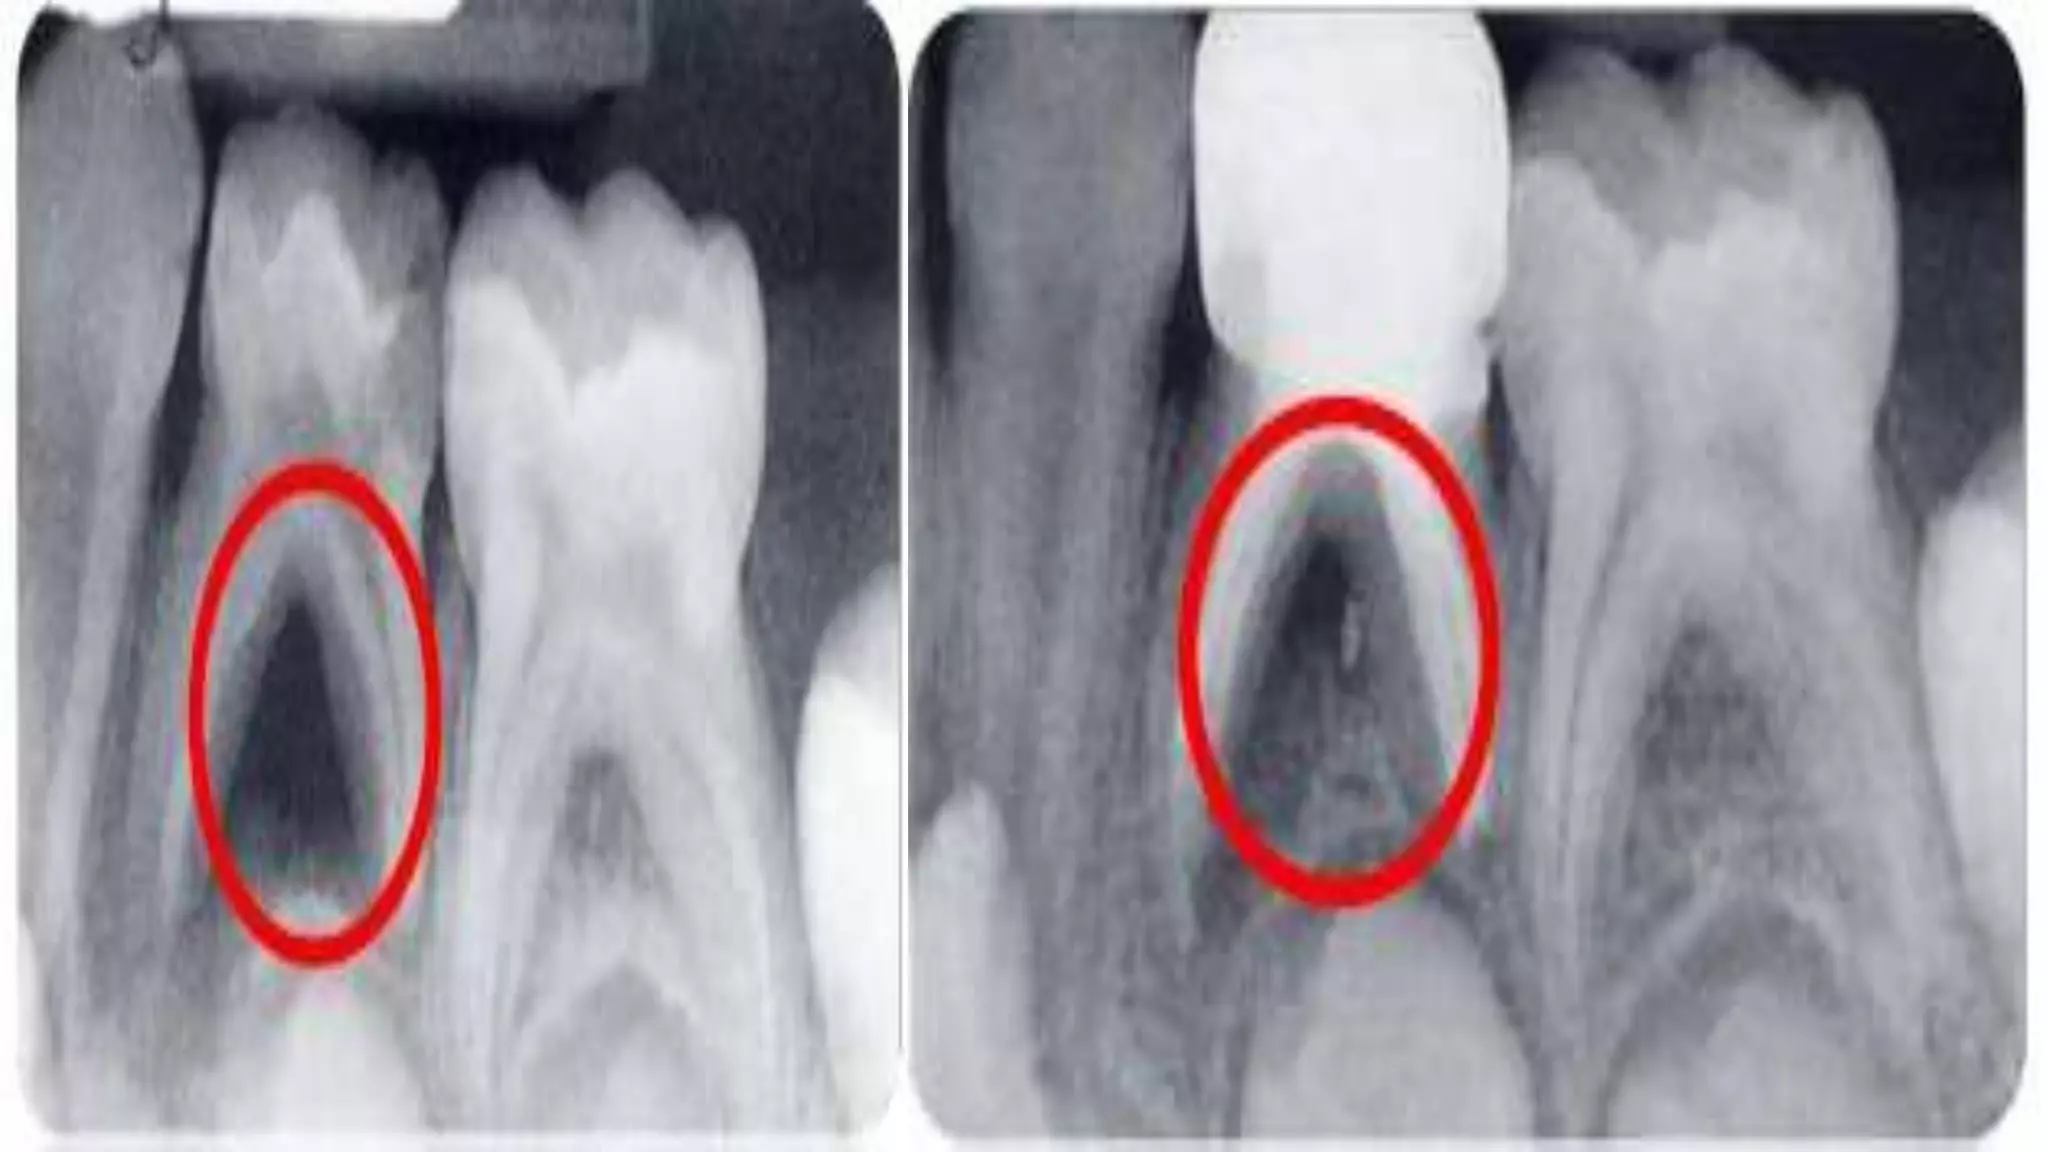

RADIOGRAPH

 BITEWING

 PERIAPICAL

RADIOGRAPHICALLY:

 NO FURTHER BONE LOSS IN FURCATION REGION

 NO EVIDENCE OF INTERNAL RESORPTION